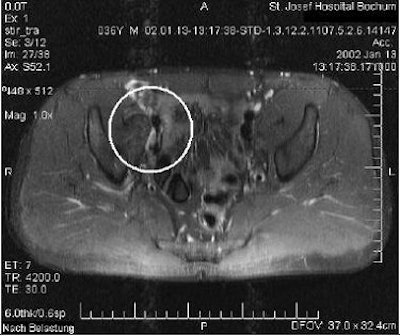

According to the results, the Valsalva maneuver provoked a visible bulge in seven patients, which was interpreted on MR as a posterior abdominal wall deficiency. In eight cases, T2-weighted STIR MR scans revealed edema in the symphysis. Three patients had adductor insertion site tenderness on physical exam, but edema was seen on MR in only one case. Overall, the 39 MRI results in 19 patients did not differ before and after physical exam, the authors stated.

![]() |

| Positive bulging provoked by Valsalva maneuver; axial plane (dynamic MRI). Reprinted from Journal of Sports Science and Medicine, Vol. 6, Daigeler A, Belyaev O, Pennekamp WH, Morrosch S, Köster O, Uhl W, Weyhe D, "MRI findings do not correlate with outcome in athletes with chronic groin pain," 71-76, 2007, with permission from the Journal of Sports Science and Medicine. |

"Thus, a repeated examination during the training period added no information to the MRI findings detected during the training-free interval," they wrote. "The pathologic findings on MRI varied neither in quality nor in quantity comparing the two different time points of evaluation, suggesting that exercise-triggered pain does not have a temporary correlate, which can be visualized by MRI."